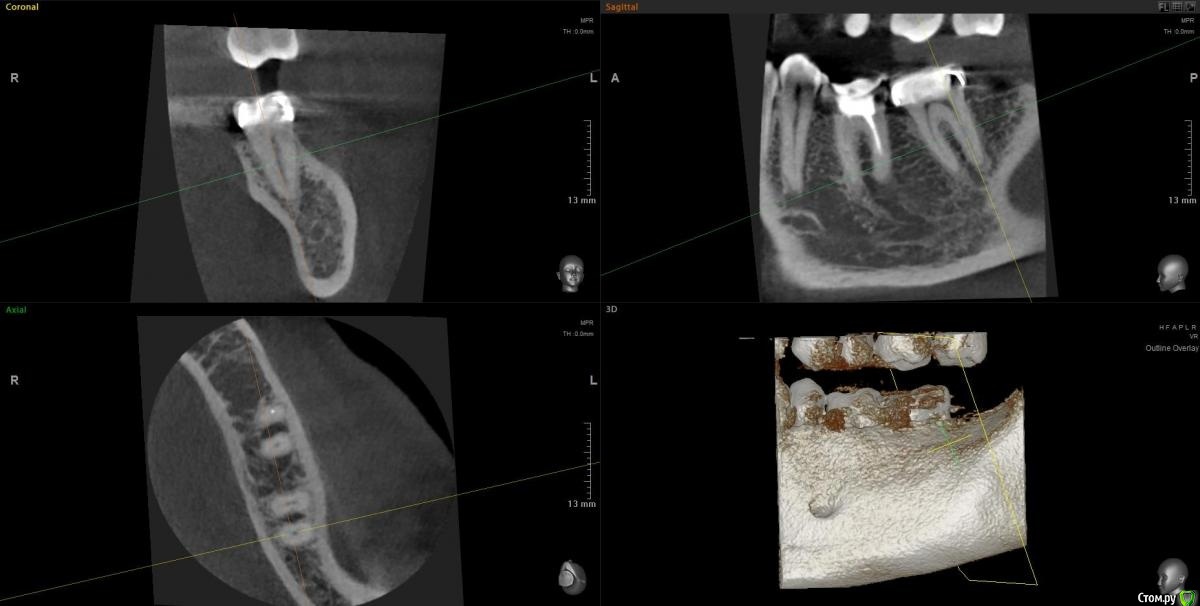

Slava76 Опубликовано 5 декабря, 2020 Поделиться Опубликовано 5 декабря, 2020 Всем доброго дня!Три дня назад с утра появилась боль в нижней челюсти слева. Сначала было не понятно, что болит зуб или мышцы. Но боль шла из под двух крайних коренных зубов. На крайнем зубе коронка, которую установил пару лет назад, зуб живой. У другого зуба пломба, которую установили около 10 лет назад, нервы удалены. Постучал чайной ложкой по этим зубам, боль не усилилась. От холодного, горячего боль так же не усиливается. К вечеру небольшая боль ощущалась только при сжимании зубов. На следующий день с утра все повторилось, с утра болело сильней, к вечеру слабей. Сходил на прием к стоматологу. Сделали снимок, см. вложение. Врач сказал, что у крайнего зуба коронка стоит хорошо, но под коронкой в зубной ткани он видит трещину. Для того, чтобы понять действительно ли она есть и какого размера посоветовал сделать КТ. У зуба под пломбой один канал не долечен, в другом сломали медицинской инструмент. Каких то воспалений он не увидел. Он считает, что боль может вызывать как один, так и другой зуб. Если есть трещина под коронкой, то вылечить зуб нельзя. Только удаление. Если "виноват" зуб под пломбой, то можно перелечить каналы и поставить коронку. В итоге сказал немного подождать, если боль не пройдет, то делать КТ и уже решать. Боль не проходит. Она не сильная, не стреляющая, терпеть ее легко. По ощущениям кажется, что боль идет от зуба под коронкой, но не уверен. Что посоветуете делать дальше? Врач, у которого был, достаточно молод. Хочется услышать еще одно мнение.Заранее благодарю за советы! Ссылка на комментарий

Slava76 Опубликовано 7 декабря, 2020 Автор Поделиться Опубликовано 7 декабря, 2020 (изменено) Сегодня сделал КТ. Выложил здесь https://cloud.mail.ru/public/2ezX/2HwT6HocyНа вечер записался к другому врачу. Послушаю, что он скажет.До обеда при нажатие была небольшая боль. Сейчас практически ее не чувствую. И так уже 4 дня. P.s.1 очень боюсь начать лечить не тот зуб. Коронку очень не хочется трогать. Ей все два года. Делала ее очень хороший врач.P.s.2 может само все пройдет... Изменено 7 декабря, 2020 пользователем Slava76 Ссылка на комментарий

Slava76 Опубликовано 7 декабря, 2020 Автор Поделиться Опубликовано 7 декабря, 2020 Вернулся от врача. Он посмотрел КТ и подтвердил слова DmitrySH. На 90% врач уверен, что проблема из-за не до конца залеченного канала и сломанного инструмента. Сказал, что нужно лечение под микроскопом. У них в поликлинике таких специалистов нет. Завтра начну искать такого врача в Нижнем Ссылка на комментарий

wladdX Опубликовано 7 декабря, 2020 Поделиться Опубликовано 7 декабря, 2020 (изменено) Трещины в зубе 37 не увидел Изменено 7 декабря, 2020 пользователем wladdX Ссылка на комментарий

DmitrySH Опубликовано 5 декабря, 2020 Поделиться Опубликовано 5 декабря, 2020 Под коронкой скорее всего не трещина, а так видно строение зуба. У зуба где сломан инструмент - есть воспаление. Начните с его лечения. Ищите эндодонтиста работающего с микроскопом 1 Ссылка на комментарий